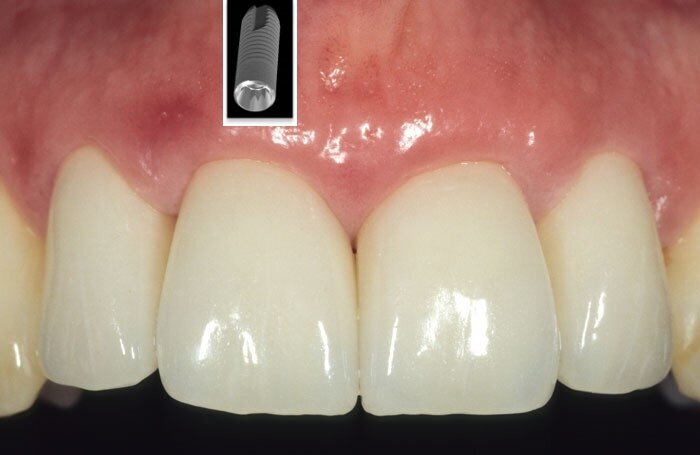

For peri-implant soft tissue, a zone of keratinized tissue is known to provide better long-term stability (Fig. 4). However, from a soft tissue augmentation perspective, either for a tooth or an implant, the buccal positioning is critical when assessing the predictability of the surgical procedure at baseline. The more buccal the implant/tooth, the harder it generally is to graft around (Fig. 5).

Fig. 4: Good soft tissue maintenance around implants can be often obtained by soft tissue augmentation, thus improving tissue biotype and keratinization.

Fig. 5. Buccal positioning of a tooth/ implant will negatively impact root coverage , and needs to be carefully assessed.